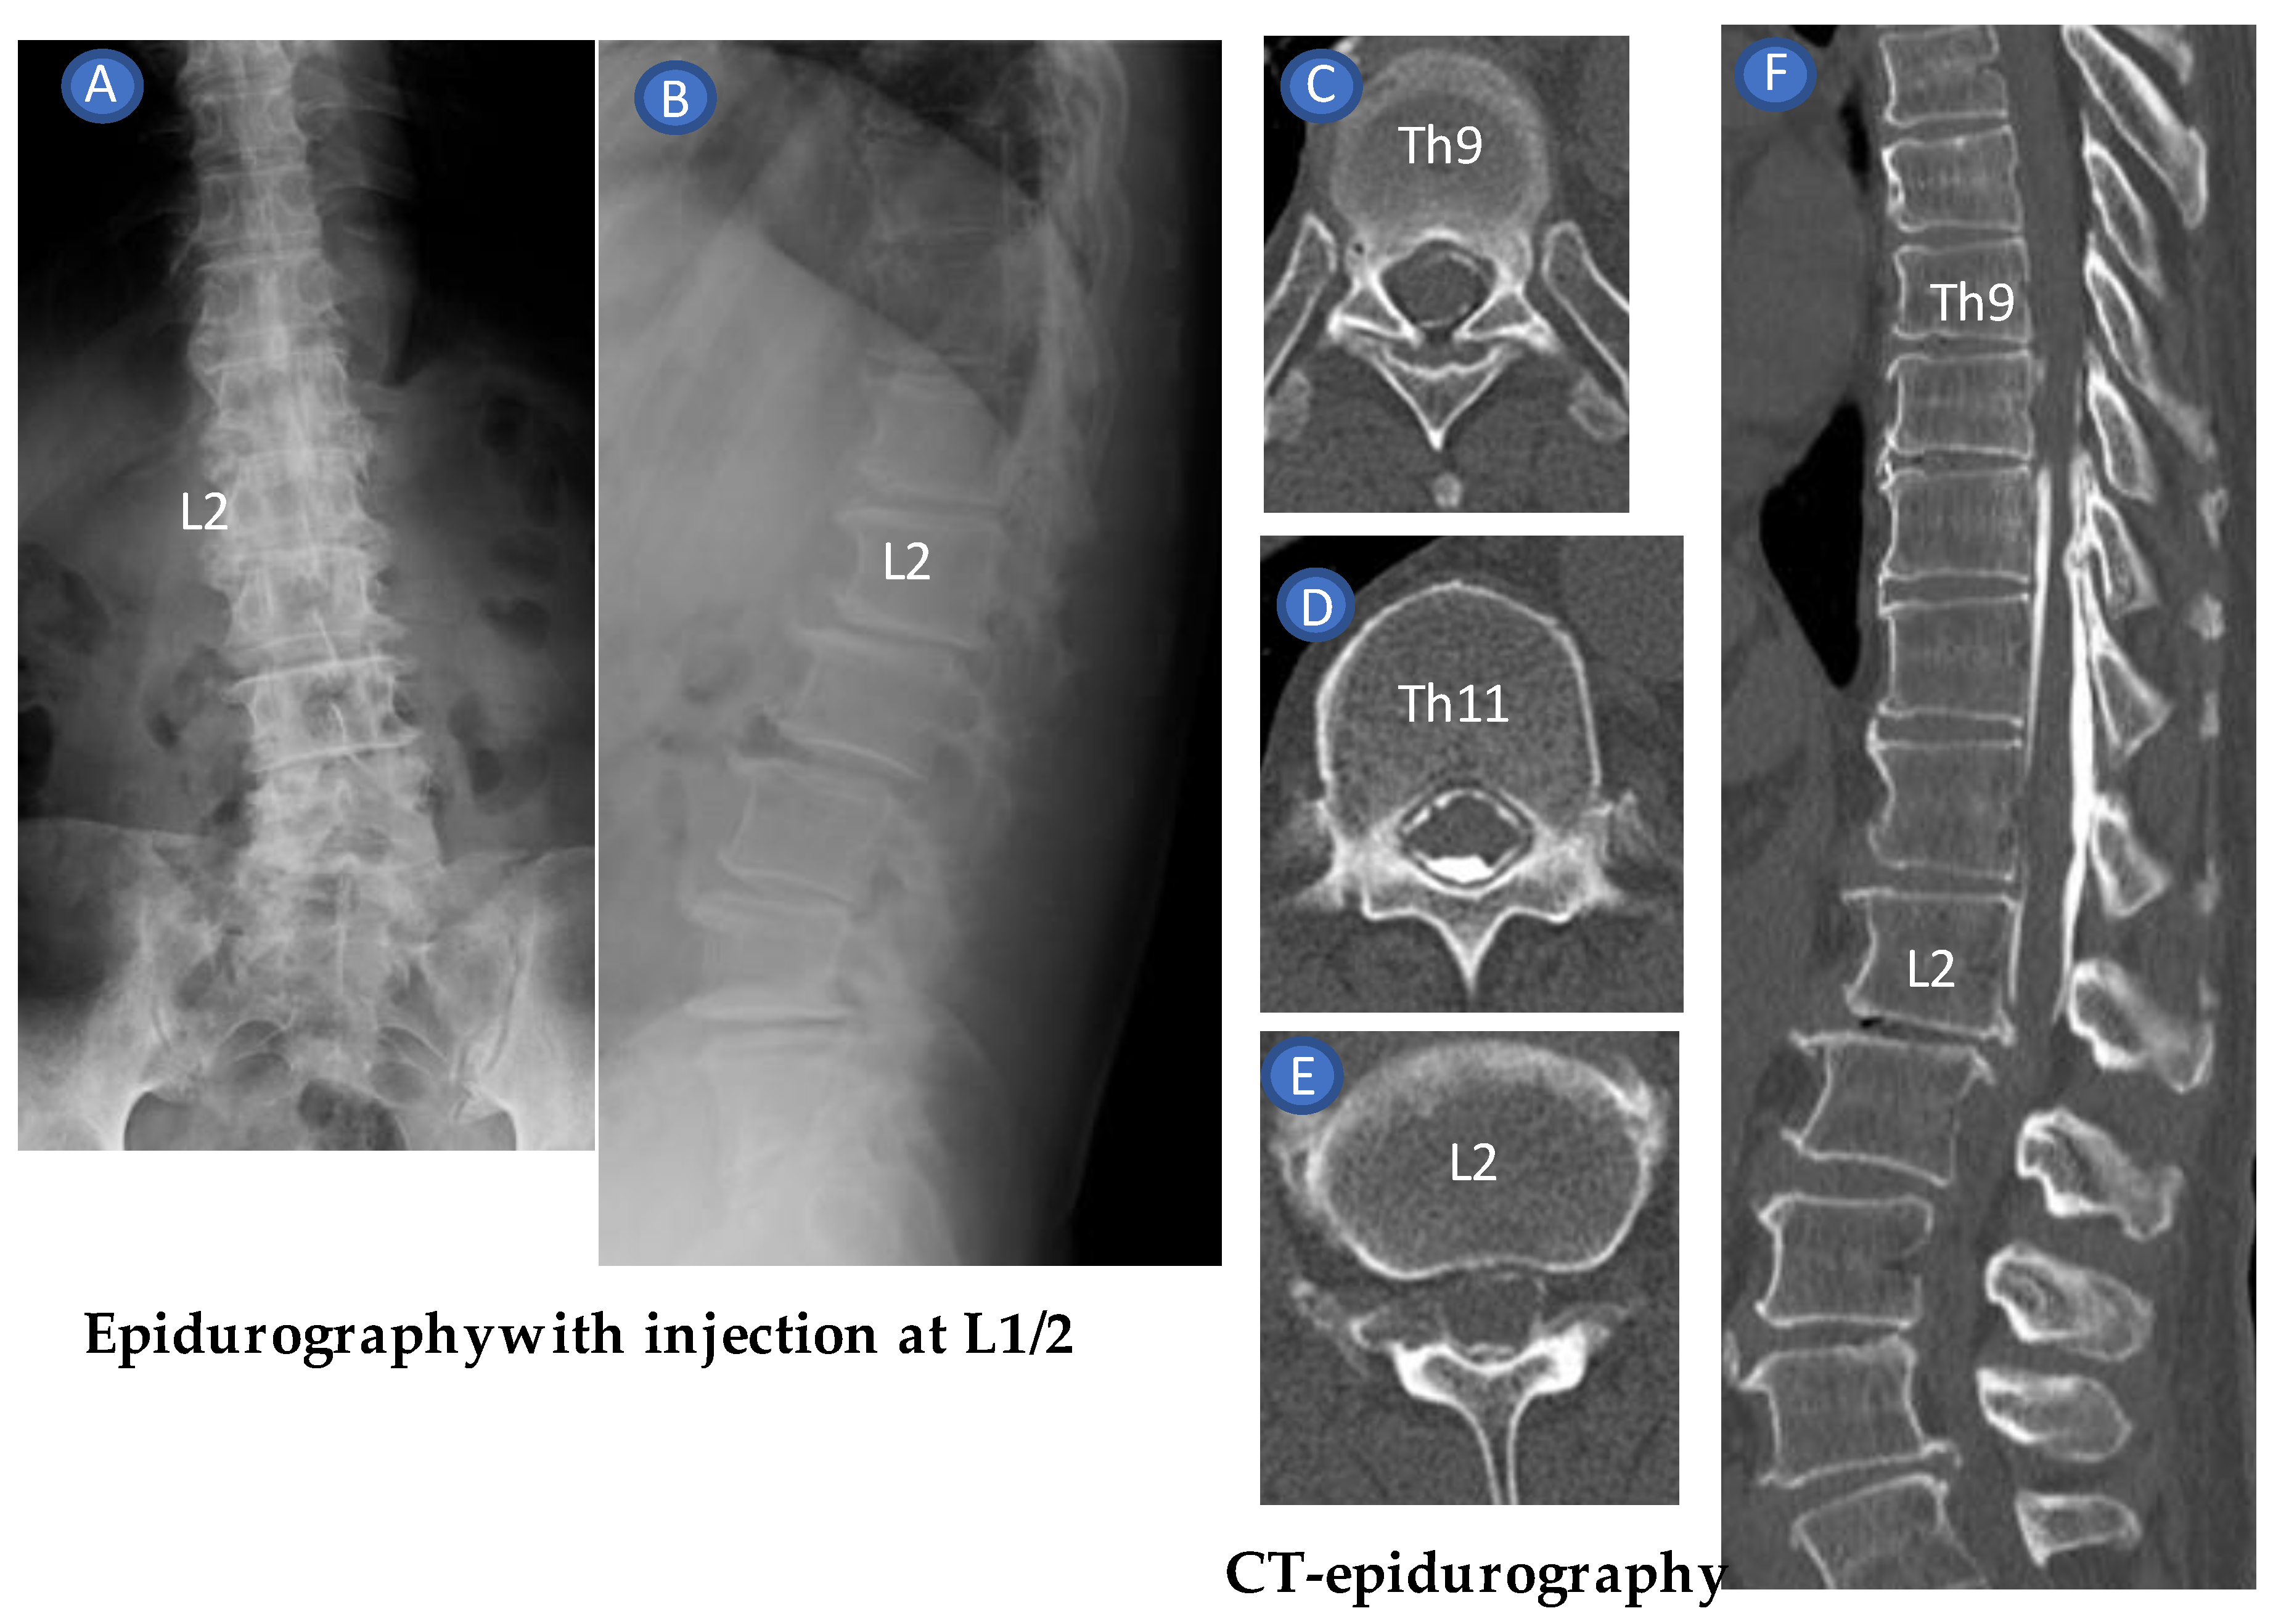

3. Case Reports